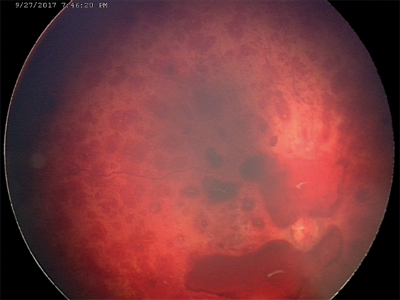

Advances in digital fundal imaging in children have transformed diagnosis and monitoring of a wide range of children’s eye diseases. RetCam and newer more portable digital fundal imaging devices (such as PanoCam) are now routinely used in infants and young children for the documentation of retinal disease (Figure 2). Digital imaging is particularly important for the diagnosis, monitoring and documentation of retinopathy of prematurity (ROP) [2]. It has significantly enabled trained non-medical users to send images obtained in the neonatal intensive care unit (NICU) to a remote expert for interpretation - true ‘telemedicine’. This principle may be transformative for the delivery of high quality ROP care in the developing world where paediatric ophthalmologists are scarce. Digital documentation of retinal haemorrhages in cases of suspected non-accidental injury is important both clinically and from a medico-legal aspect (Figure 3).

Figure 3: RetCam images of child with suspected non-accidental injury

with bilateral multi-layered retinal haemorraghes.

The images obtained are important evidence for subsequent hearings in both the family and criminal courts. Optos widescreen digital imaging can be carried out from at least four years of age in a cooperative child and provides quickly captured wide angle images (Figure 4). These are excellent for assisting the clinician in diagnosis and monitoring of both paediatric retinal disease, retinoblastoma and posterior uveitis. Fluorescein angiography and the autofluorescence functions of digital imaging systems have similarly assisted accurate diagnosis and delineation of maculopathy, retinal ischaemia and subretinal neovascular membranes in paediatric retinal disease.